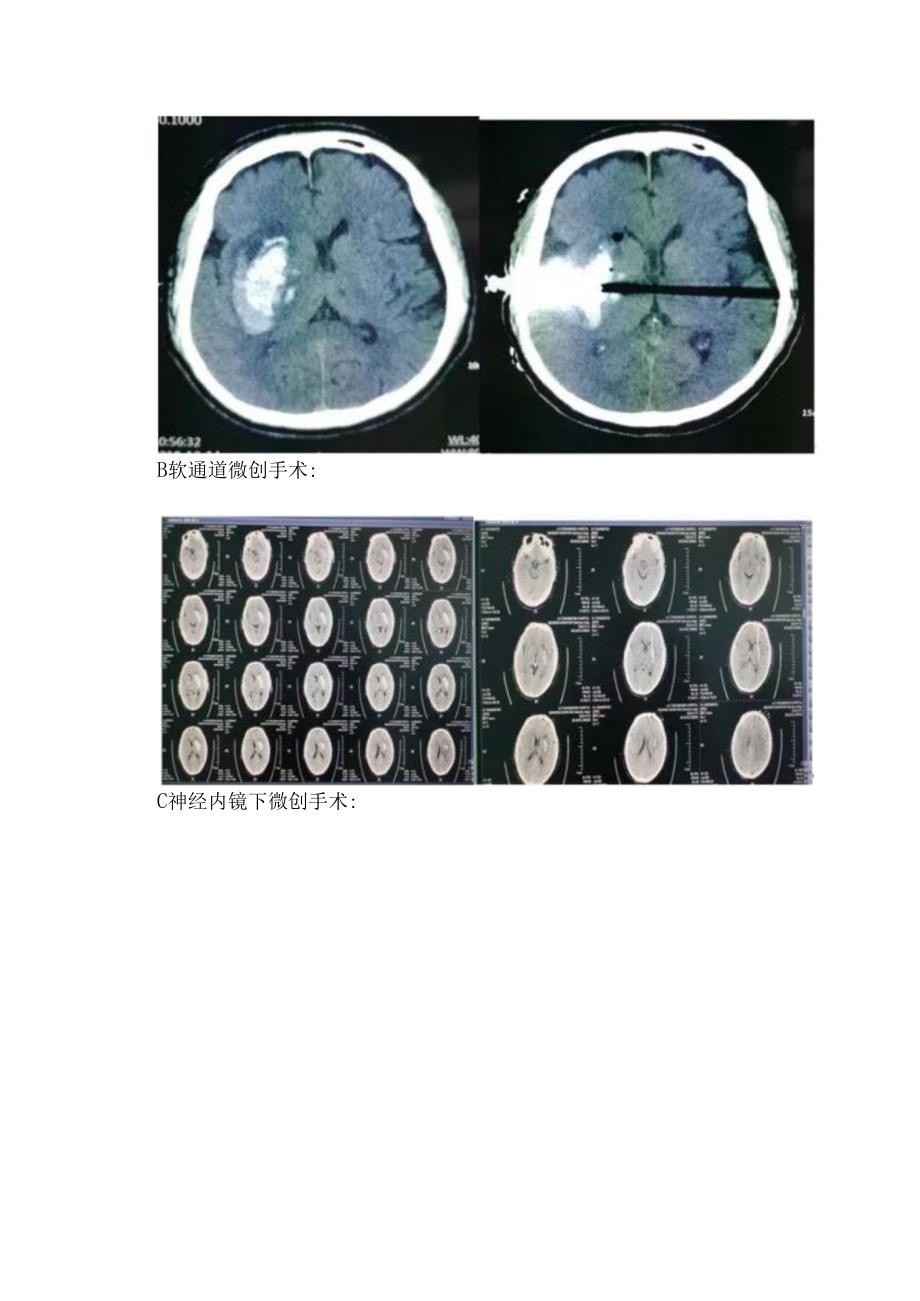

2、浆中的脂质易通过破损处进入内膜,使动脉壁发生脂肪玻璃样变或纤维素样坏死,增加了血管壁的脆性,当情绪激动、劳累或用劲排便等原因,造成血压进一步增高,就易引起血管破裂,发生脑出血。脑出血的原因除了高血压外,还有脑血管的畸形(年轻人脑出血的主要原因)、脑外伤、脑肿瘤和血液病。三:脑出血易发生部位脑出血可以发生在脑实质的任何部位,可以单发,也可以多发。但大多数高血压脑动脉硬化性脑出血多为单发。其好发部位为基底节区,出血多发生在豆纹动脉,因此,有人称豆纹动脉为“出血动脉”,外囊、桥脑、脑叶、小脑等部位出血相对较少。大脑基底节,占70%,包括外囊和丘脑;桥脑出血,占10%;脑叶出血,占10%,额叶、颗叶、枕叶均可发生,以顶颗部多发;小脑出血;占10%脑室出血,靠近脑室的脑出血破入脑室称继发性脑室出血。脑CT应用于临床后,脑出血的诊断和分型很细致,是为了选择手术的适应证和估计预后而划分的。四:脑出血治疗方法1内科治疗2外科治疗A硬通道微创手术:B软通道微创手术:C神经内镜下微创手术:D开颅手术: